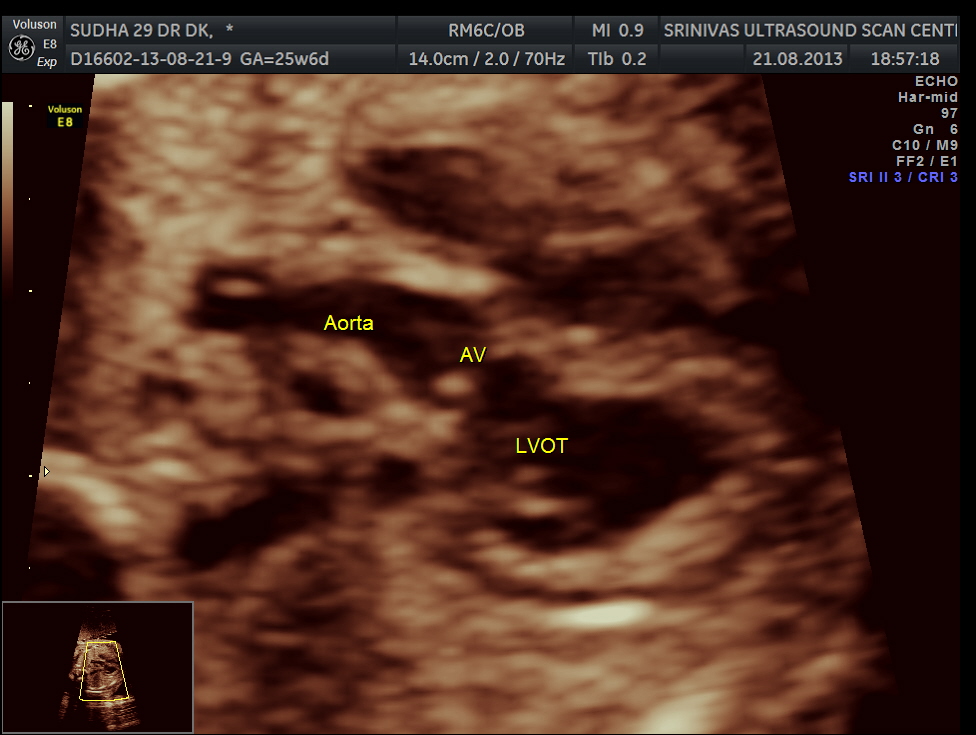

Under normal circumstances the chamber in front of descending aorta is left atrium ; and the aorta arises from the left ventricle which has no trabeculations ; the pumonary artery which divides into the two branches arises from the anterior right ventricle and crosses over the aorta .

some normal images are given below to compare with the latter images.

next is the normal outflow tracts and the normal 3 vessel view and the normal arches.

here we can see the pulmonary artery with its two branches arising from the lower (left) ventricle .and the aorta arising from the anterior (right ) ventricle.